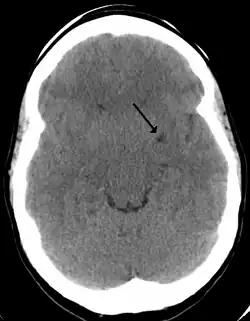

Les espaces de Virchow-Robin, encore appelés espaces périvasculaires, doivent leur nom à Rudolf Virchow et Charles Philippe Robin. Ce sont des espaces, souvent uniquement virtuels, qui entourent les vaisseaux sanguins pendant une courte distance alors qu'ils entrent dans le cerveau. Ces espaces se trouvent donc entre d'une part la paroi des vaisseaux et d'autre part l'intima pia qui est la couche avasculaire de la pie-mère. Ils forment des sortes de gaines, sous arachnoïdienne et sous piale, entourant les artérioles pénétrant dans le cortex, et remplies de LCR.